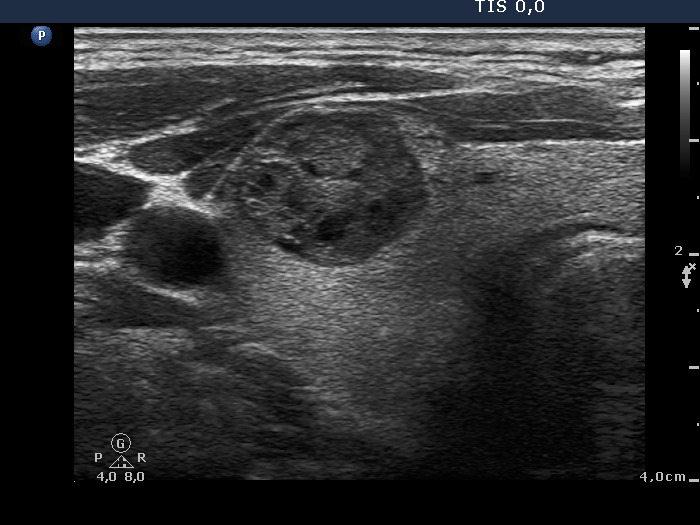

Benign cystic-colloid goiter (cytological diagnosis) - case 123 |

Intrathyroidal parathyroid adenoma (histological diagnosis) - case 1399 |

The synchronous presence of hyperechogenic lines and granules proves that these figures represent connective tissue while one in the ventral part does represent a colloid crystal.

There are a few hyperechogenic granules within the small lesion and we can see two much thinner lines, as well. These figures might be either punctate echogenic foci or non-specific granules of a normal connective tissue.